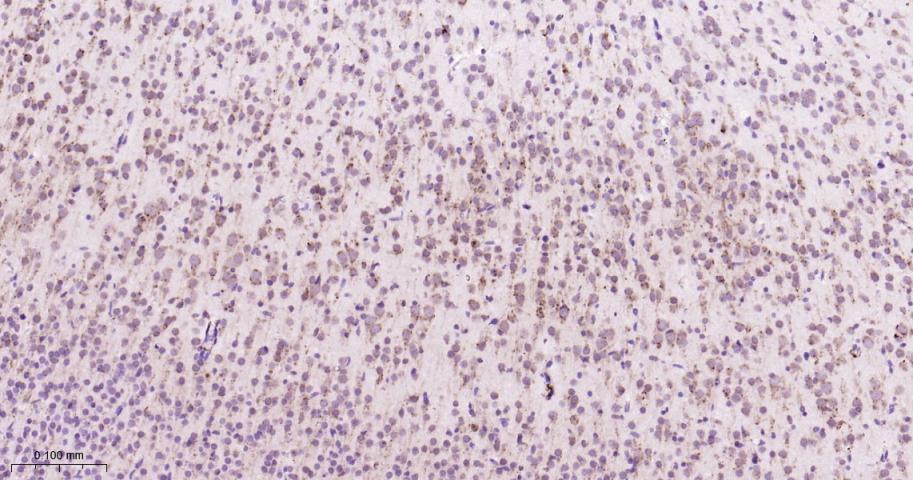

Paraformaldehyde-fixed, paraffin embedded Human Cerebrum; Antigen retrieval by boiling in sodium citrate buffer (pH6.0) for 15 min; Antibody incubation with GRP94 Monoclonal Antibody, Unconjugated(bsm-61455R) at 1:200 overnight at 4°C, followed by conjugation to the bs-0295G-HRP and DAB (C-0010) staining.

Paraformaldehyde-fixed, paraffin embedded Rat Cerebrum; Antigen retrieval by boiling in sodium citrate buffer (pH6.0) for 15 min; Antibody incubation with GRP94 Monoclonal Antibody, Unconjugated(bsm-61455R) at 1:200 overnight at 4°C, followed by conjugation to the bs-0295G-HRP and DAB (C-0010) staining.

Paraformaldehyde-fixed, paraffin embedded Mouse Cerebrum; Antigen retrieval by boiling in sodium citrate buffer (pH6.0) for 15 min; Antibody incubation with GRP94 Monoclonal Antibody, Unconjugated(bsm-61455R) at 1:200 overnight at 4°C, followed by conjugation to the bs-0295G-HRP and DAB (C-0010) staining.